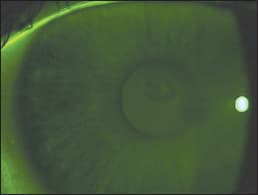

Presenting corrected visual acuities were: OD 20/25 and OS 20/20. Over-refraction did not further improve her vision. After removing her lenses, biomicroscopy revealed a perfectly circular area of negative staining positioned directly over the visual axis. No infiltrates or breaks in the epithelium were apparent. The anterior chambers were devoid of cells or flare, and there was no conjunctival injection.

The patient returned in one week and reported that her vision was worse, but that she still had no pain or discomfort. She reported wearing her lenses on a very limited basis, for games and practice. Corrected acuities were: OD 20/30 OS 20/20. Examination revealed virtually no change in elevation of the lesion, which we confirmed by corneal topography. A new finding was the presence of sub epithelial infiltrates directly beneath and limited to the area of the lesion, which was still perfectly round in shape. Our new diagnosis was corneal infiltrate underlying a focal discrete area of epithelial edema. We instructed the patient to continue the hypertonic therapy but added Lotemax (Bausch + Lomb) ophthalmic suspension every four hours in the affected eye.